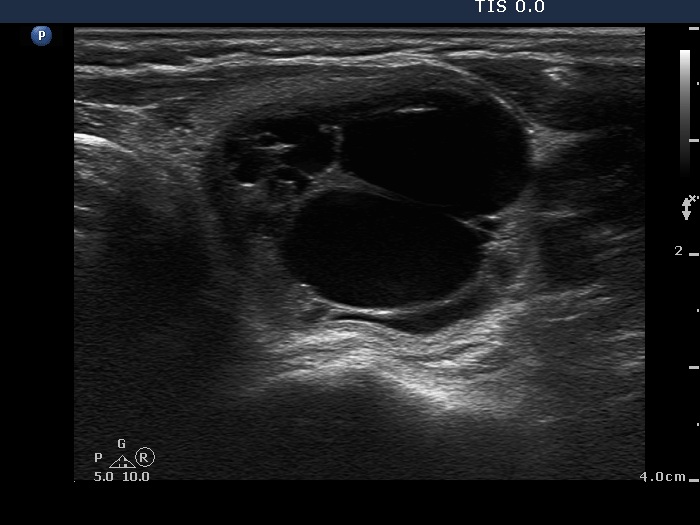

Follicular adenoma (histological diagnosis) - case 486

The dorsal wall of the small cystic areas presents posterior back wall enhancement. The origin of the large granules within the solid part remains obscure; nevertheless these are probably colloid crystals.